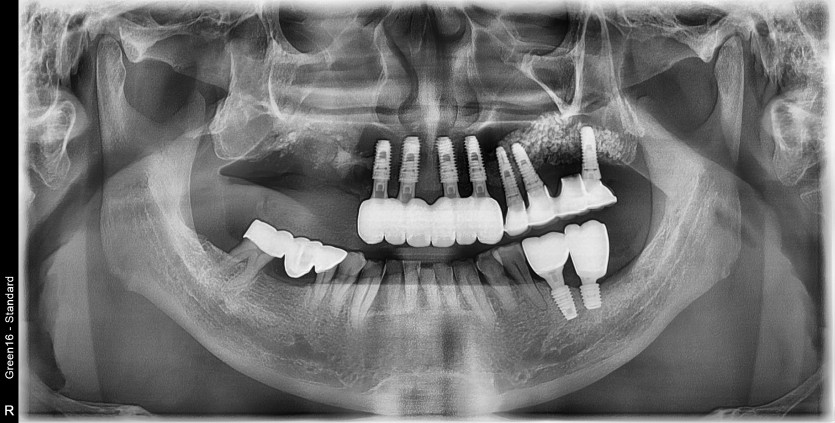

10번대 픽스쳐 파절로 임플란트 재수술 진행